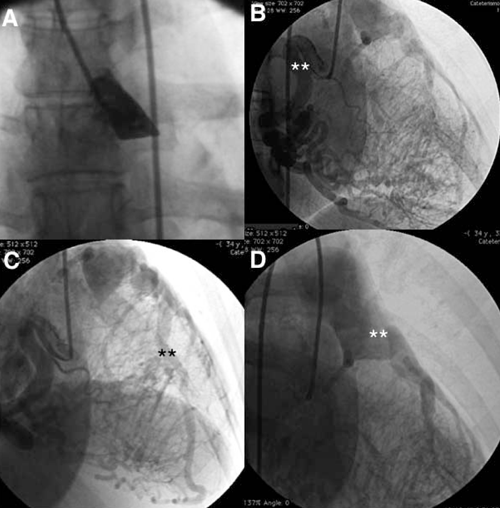

Con diagnóstico presuntivo de ALCAPA se realizó CACG que confirmó el nacimiento anómalo de la ACI desde la AP (figura 1).

Coronariografía. A) Ausencia de la arteria coronaria izquierda en el seno de Valsalva izquierdo. B) Arteria coronaria derecha dilatada, flexuosa (**), con importante red de colaterales septales. C) Arteria descendente anterior ectásica (**), que recibe flujo desde la arteria coronaria derecha. D) Nacimiento de la arteria coronaria izquierda desde la arteria pulmonar (**).